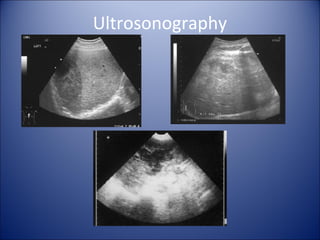

• Ultrasonography (FAST)

--fast, accurate, noninvasive, a good initial screening test

--sensitivity 88%, specificity 99%, accuracy 97%

Ultrosonography